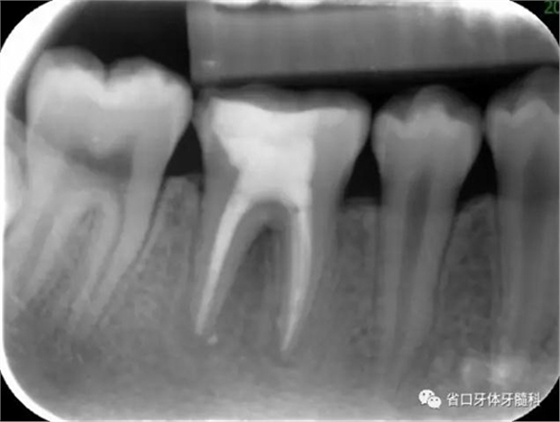

圖3 根管治療術后4個月